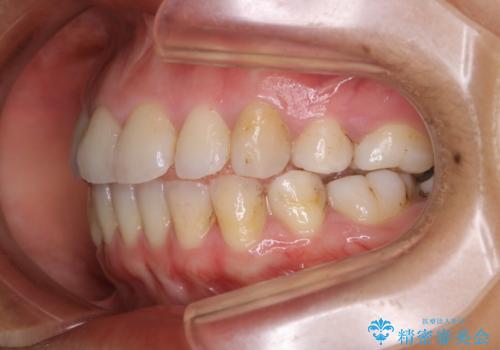

タバコをよく吸う方で1年ぶりのクリーニングになるそう。ただ、昔から着色が付きやすく取れないとのこと。

エアフローを使いましたが、汚れはとても頑固で、元々歯の面に多くの凹凸があり、その隙間に入り込んでいる着色、虫歯の初期による変色以外を除去していきました。60分でも時間は足りませんでした。